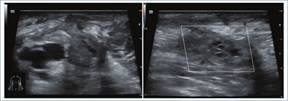

Los hallazgos ecográficos pueden ser:

Directos: ausencia de flujo en la evaluación Doppler color y espectral, falta de compresibilidad de la vena, visualización de material ecogénico endoluminal (según el estadio de evolución) (Fig. 2)3,4.

Indirectos: flujo de alta resistencia (tri- o bifásico) previo al sitio de trombosis y baja VPS posterior al sitio de trombosis3. Estos hallazgos pueden ser similares a los de una estenosis (Fig. 3)4.